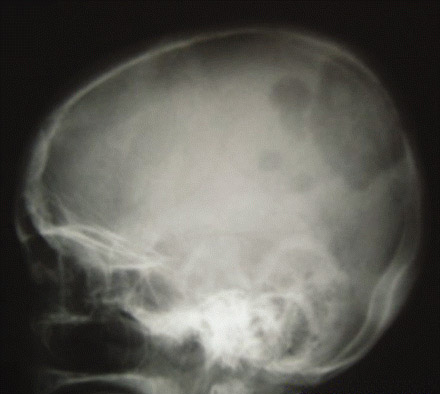

Skull x-ray showing extensive metastases from follicular thyroid carcinoma

Wani AM, Hussain WM, Fatani MI, et al. Skull metastases from thyroid carcinoma. BMJ Case Reports. 2009; doi:10.1136/bcr.02.2009.1578